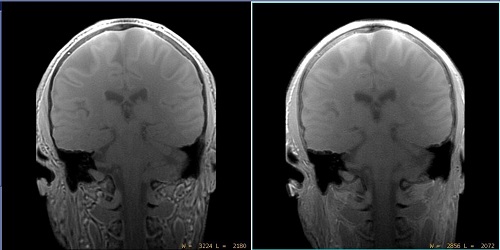

Figure 1. Example of Chemical Shift Reduction off and on with head scan

Table 1. Image legend

SideDescription

LeftChemical Shift Reduction turned off.

RightChemical Shift Reduction turned on.

• For water dominant anatomies such as the brain, turning on Chemical Shift Reduction results in more blurriness.

• Recommended for use with musculoskeletal scans and not for brain scans.